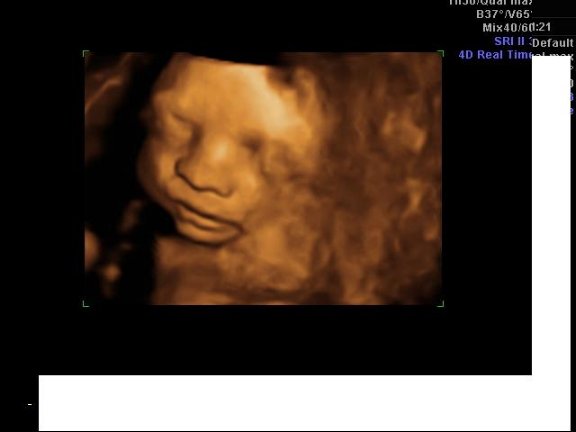

Rakok 4D képet Milánról.Nagyon jó volt csak iszonyat álmos volt a ksfiam.Egyfolytában ásítozott: Kép Kép